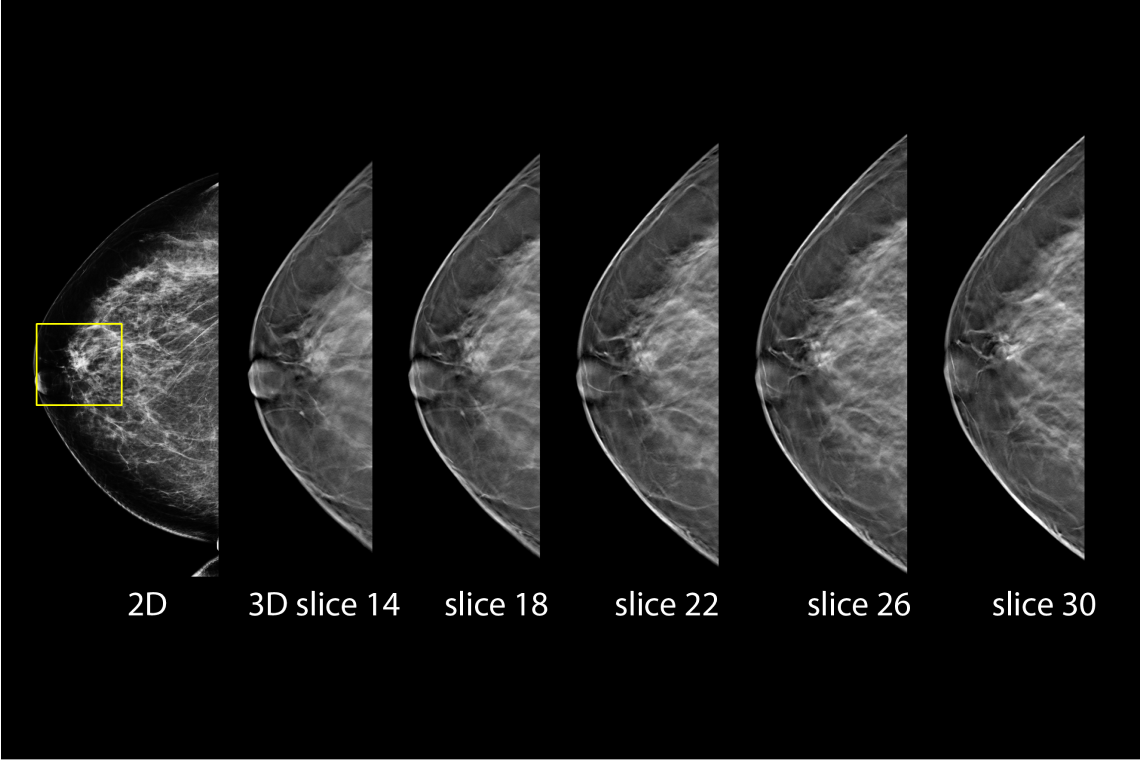

Hologic has further advanced breast cancer screening by producing 2D images from breast tomosynthesis data using C View software, resulting in a Low Dose Genius 3D Mammography exam with superior clinical performance compared with 2D alone.4

This Low Dose Genius 3D Mammography exam is performed in a rapid 3.7 second scan time for greater patient comfort and low patient dose, due to the elimination of 2D X ray exposures. The synthetic 2D images and 3D slices are reviewed together to make clinical decisions or diagnoses part of the Genius 3D Mammography screening exam.